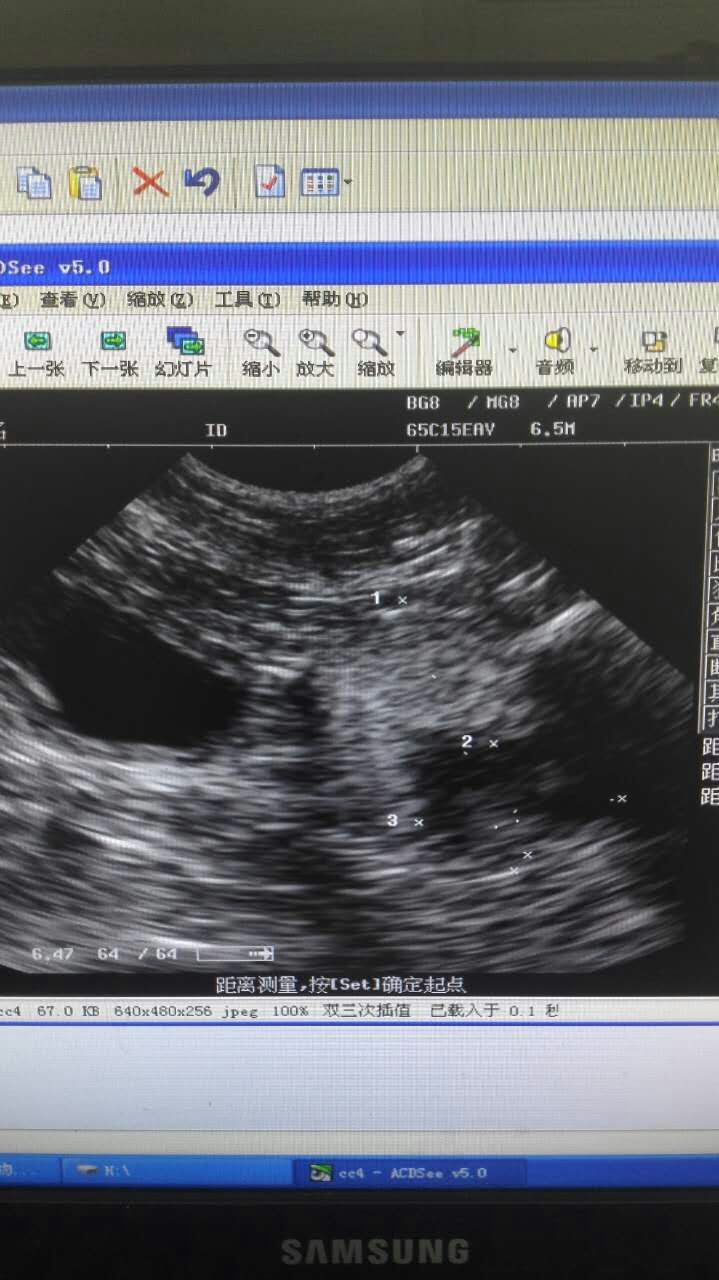

比熊犬,丑丑,雄性,3岁多。2016年5月16日,主人因丑丑尿血带来检查,检查后发现膀胱粘膜增厚,前列腺增大、囊肿。保守治疗两天后,未见明显好转,与主人沟通后,采取B超引导穿刺前列腺囊肿,抽取囊液,并行去势术,术后常规消炎7天。半月后复查,B超未探及囊肿,前列腺萎缩。小便正常,食欲精神正常。